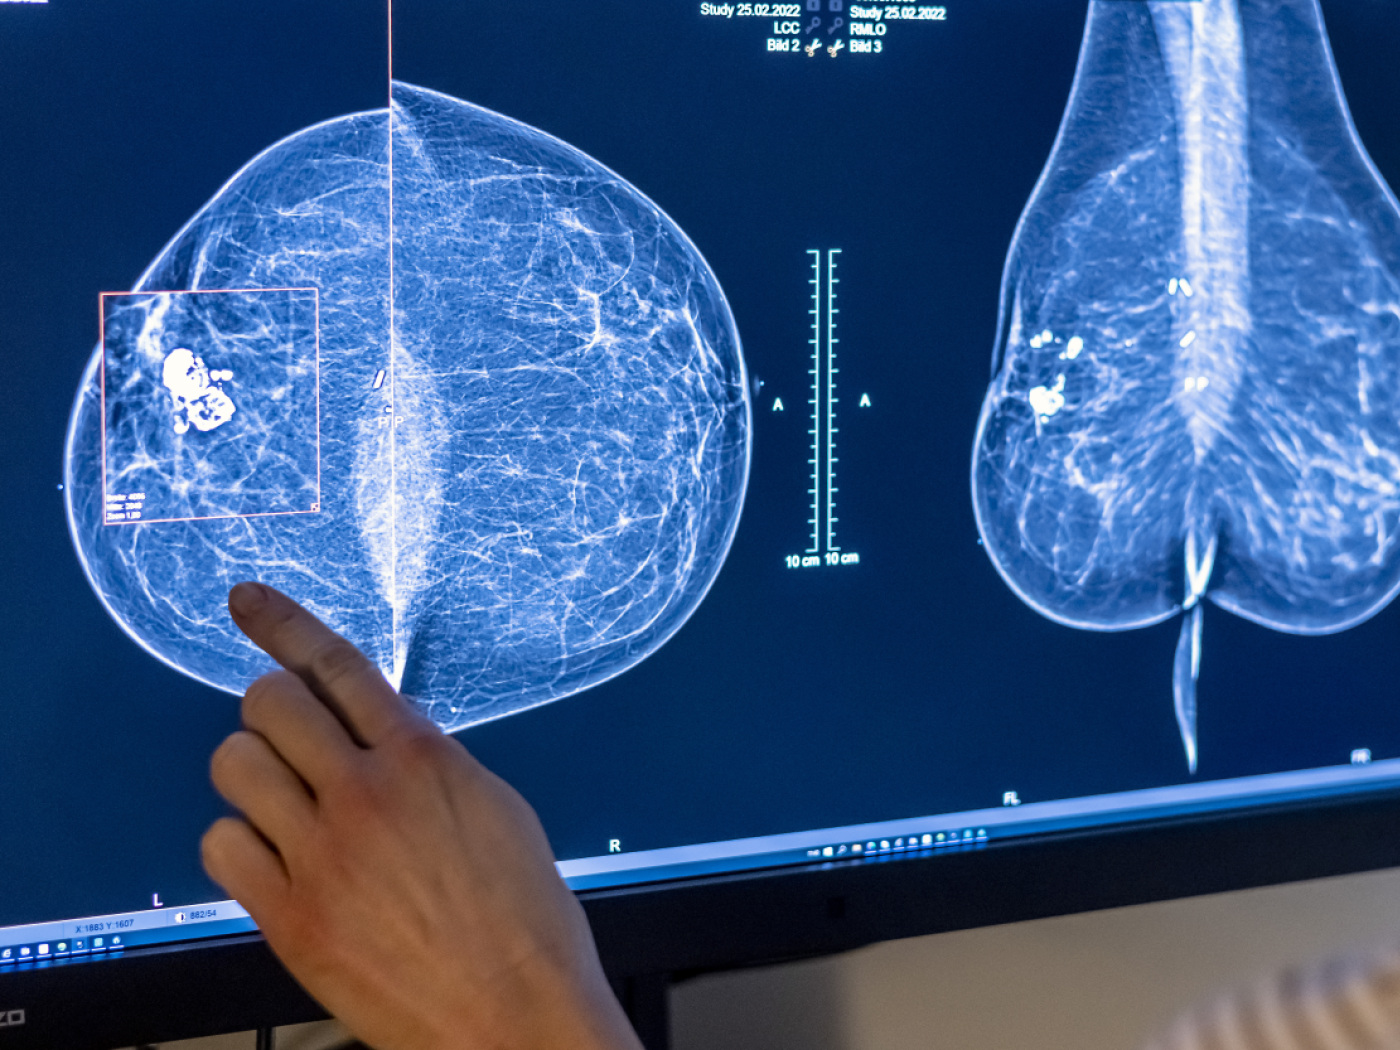

Der Baselbieter Landrat hat sich am Donnerstag für ein kantonales Krebsregister ausgesprochen. Es soll Daten an die Früherkennung weiterleiten, solange Patientinnen und Patienten nicht widersprechen. Die Vorlage wurde mit 71 zu 8 Stimmen ohne Enthaltungen angenommen.

(Keystone-SDA) Die Änderung des Gesundheitsgesetzes sieht die Führung eines kantonalen Krebsregisters vor. Zur Qualitätssicherung soll dieses persönliche und diagnostische Daten von Patientinnen und Patienten an Früherkennungsprogramme weiterleiten. Im Zentrum stehen sogenannte Intervallkarzinome, also Krebserkrankungen, die zwischen Untersuchungen auftauchen.